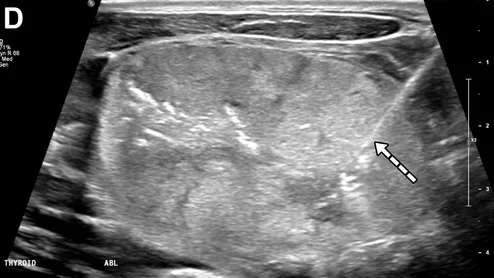

Philips UroNav system gains FDA clearance

The fusion technology integrates pre-procedural MR images of the prostate with intraprocedural ultrasound images in real-time.